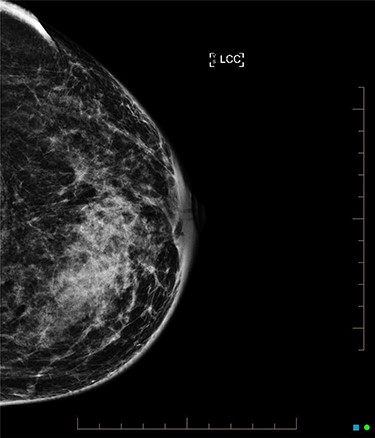

Core biopsy of the right breast demonstrated a high-grade ductal carcinoma in situ (DCIS) (Fig. 4), whilst staging computed tomography and bone scan showed no evidence of distal disease. Magnetic resonance imaging (MRI) identified a resectable 60-mm area in the right outer quadrant. AB underwent an oncoplastic right wide local excision with sentinel lymph node biopsy (SLNB), subsequently requiring an axillary dissection due to macrometastatic axillary disease. Histopathology showed multifocal high-grade invasive ductal carcinoma with immunotyping of Grade 3, PR ++, HER-2 negative, resulting in an adjuvant chemotherapy regime of cyclophosphamide and doxorubicin. The left breast was monitored without change during this time. Fully fractionated whole breast radiotherapy with boost to the tumor bed and regional lymph nodes is scheduled, alongside risk reducing endocrine therapy.